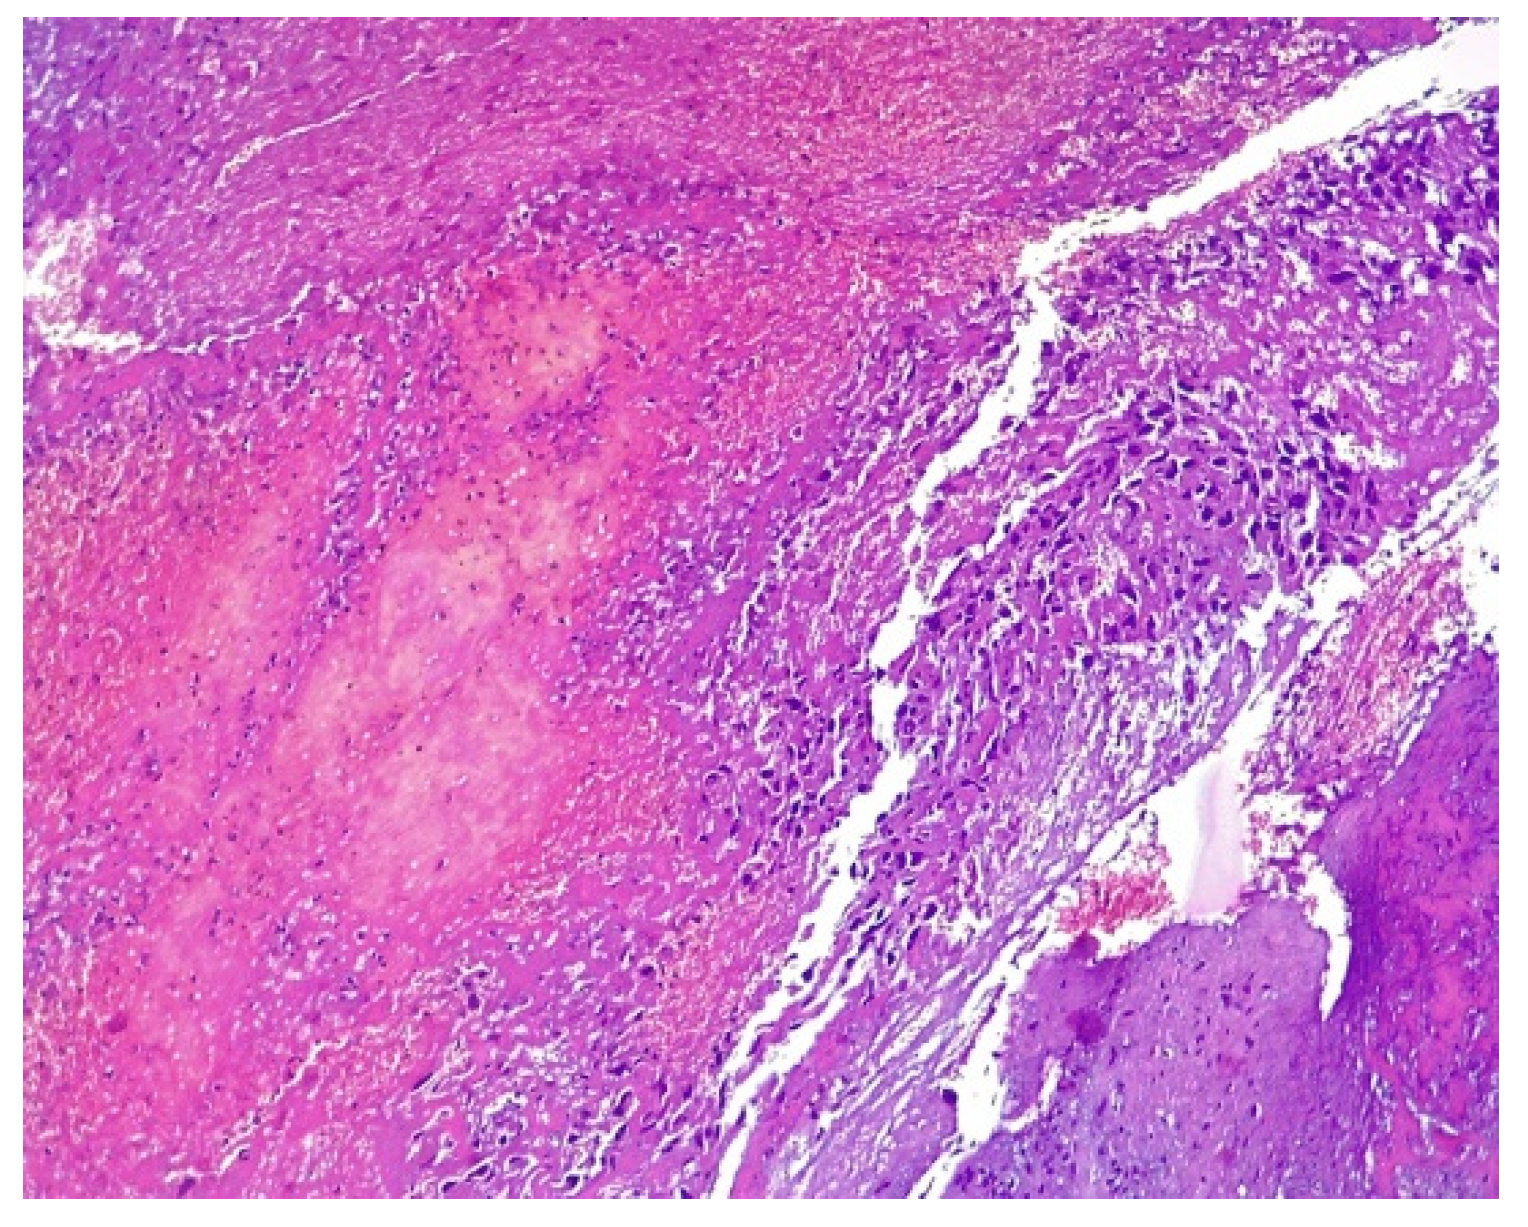

2. Case Presentation